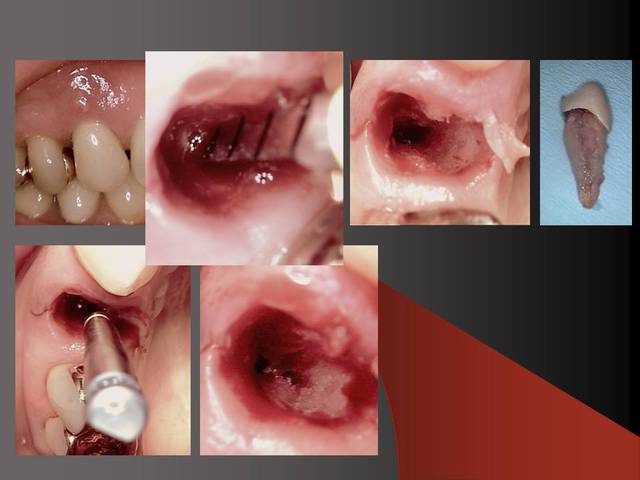

Photo 2 du dernier cas, je crains beaucoup pour la plaque d'os en vestibulaire, même en flapless.

:-) oui moi aussi j´ai eu peur ;-)

Plus sérieusement ,si la patiente avait eu un gummy smile alors je aurai rajouté de l´os. Mais ca fonctionne comme ca (en flapless + condensation )dans le temps. Je vais regarder pour retrouver la radio contrôle du cas.

Oui sans condenser juste en flapless ca serai moins évident. Pour moi-même en condensant j´ai besoin de 1 mm buccal minimum(plus il y a mieux c´est) mais dans ma pratique et celles mes confrères ca fonctionne et cela dure dans le temps depuis 16 ans.

En dessous il y a des photos, dans une on voit (troisième) qu il n y a pas de resorption de l´os après 14 ans, ce que l´on voit c´est l´os très fin condensé sur l´implant.

Le premier photo c´est une erreur parce que le périoste est blessé et les foret "trop" grands.